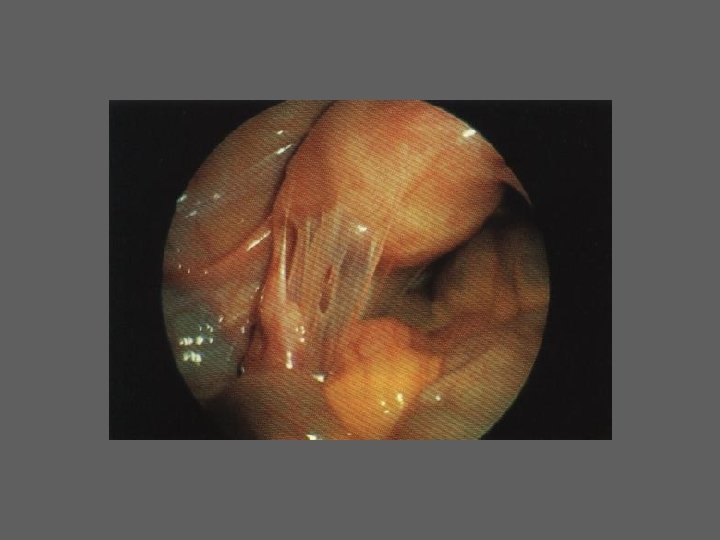

HISTEROSCOPIA - INDICAÇÕES Todas a situações em que se julgue vantajosa uma visualização completa da cavidade uterina, em particular: – Metrorragias – Dismenorreia adquirida – Infertilidade – Abortamentos de repetição e parto pré-termo – HSG anormal – DIU “perdido” – GIFT e ZIFT – Tratamento cirúrgico da patologia intracavitária: ● pólipos, miomas, septos, sinéquias, recessões endometriais ● baixos custos, reduzida morbilidade